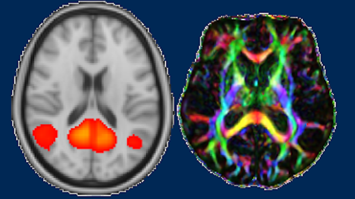

Mitochondrien sind die Kraftwerke der Zellen. Sie wirken als mikroskopisch kleine Elektromotoren des Lebens. Die Zellatmung in den Mitochondrien wandelt mithilfe von Sauerstoff die Kalorien der Nahrung in nutzbare Energie um, die wir für Wachstum, Bewegung, Denken, oder Regeneration benötigen. Proteine sind wichtige Bauelemente und molekulare Maschinen im Körper. Sie bauen Gewebe auf, schützen vor Infektionen und regulieren den Energiestoffwechsel in den Mitochondrien. Die Messung der Zellatmung und der Proteinmaschinerie durch ’MitoAnalytics’ ermöglicht es, Krankheitsmechanismen, zum Beispiel bei Krebs, Morbus Parkinson und degenerativen Erkrankungen zu verstehen.

Oroboros Instruments und KinCon biolabs setzen ihre Technologien in den frühen Phasen der Medikamentenentwicklung ein. Wirkstoffe sollen nur an bestimmten Stellen im Körper eingreifen – zum Beispiel an einem bestimmten Protein. Unerwünschte Nebenwirkungen, wenn sich ein Medikament zusätzlich an anderen Stellen nachteilig auswirkt, sollen vermieden werden. Diese Kooperation eröffnet neue diagnostische und therapeutische Perspektiven und fördert eine zukunftsorientierte, personalisierte medizinische Versorgung.